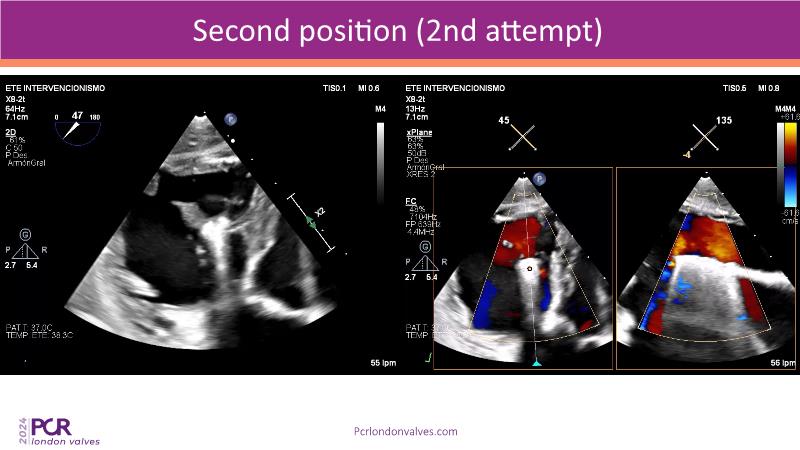

This session examines two compelling cases: a 78-year-old woman with paroxysmal atrial fibrillation, chest trauma, an osteoporotic sternum fracture, and NYHA II exertional dyspnoea, and an 82-year-old man with chronic three-vessel coronary artery disease, bradycardic AF, peripheral arterial disease, spinal stenosis, and chronic kidney disease. Through their study, discover the intricate anatomy of atrioventricular valves, the therapeutic challenges they pose, and the growing significance of transcatheter edge-to-edge repair (TEER) therapies. The discussion also highlights the value of multidisciplinary strategies in managing complex valve diseases effectively.